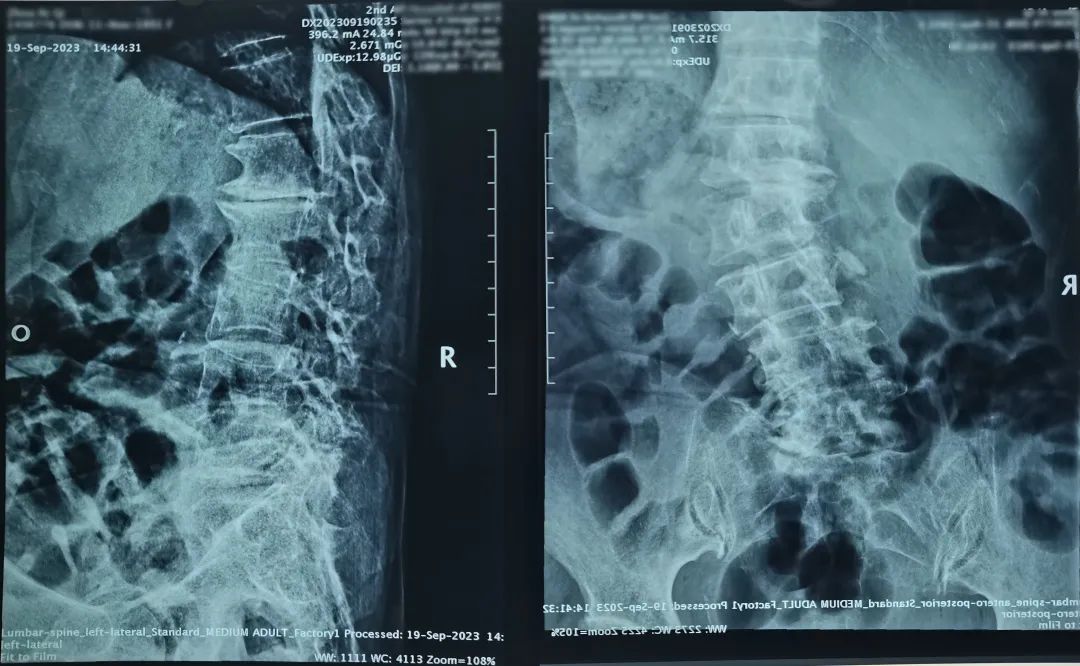

Preoperative X-rays and MRI revealed multisegment spinal pathologies in the patient, characterized by deviations from the normal anatomical position, spinal deformities, and vertebral hypertrophy, making the surgery more challenging and demanding precision in surgical techniques. After comprehensive evaluation by the consultation team, it was decided to perform a "Lumbar Spinal Posterior Fusion and Fixation" surgery with the assistance of a surgical robot due to the patient's unique anatomical circumstances.